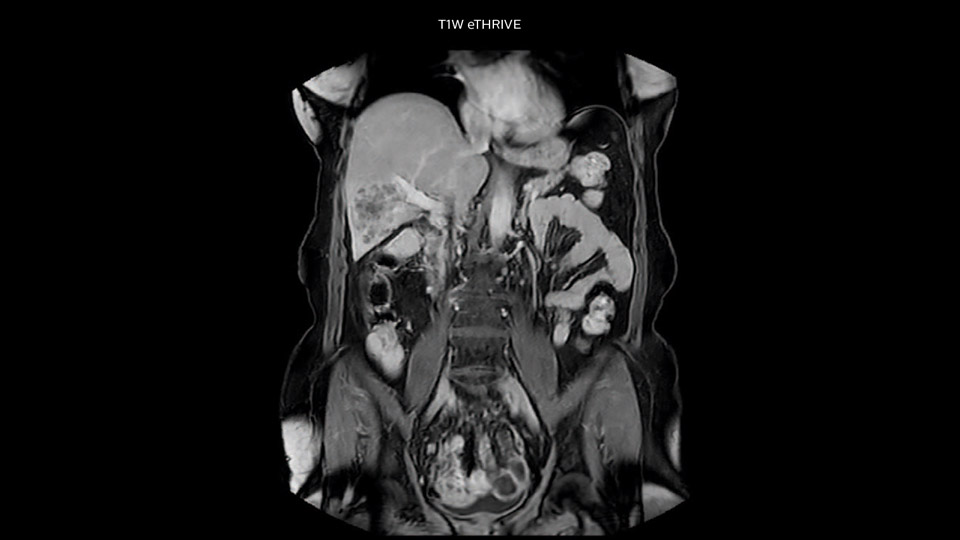

Comparison of liver MRI with and without MultiVane XD motion correction

In this example the image quality of the MultiVane XD images is evidently better than in the images without MultiVane XD. Ingenia 1.5T with dS Torso coil solution.

“We include mDIXON for the dynamic sequences because of the robust and homogeneous fat suppression we get with that. We had been using eTHRIVE, but we are now quite happy with mDIXON. Sometimes we use a medication to calm the bowels, to further improve the image quality.”